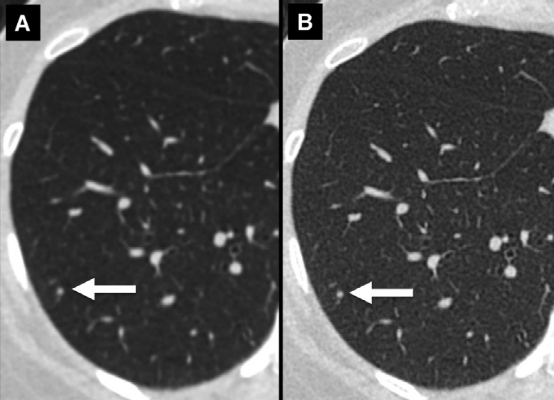

左肺上叶A、B,实性结节 (箭头)。左肺下叶C、D,亚实性结节 (箭头)。

与B和D相比,由于部分容积效应,A和C上的实性和亚实性结节边界显示较差。此外,D更好地显示出结节的实性成分。